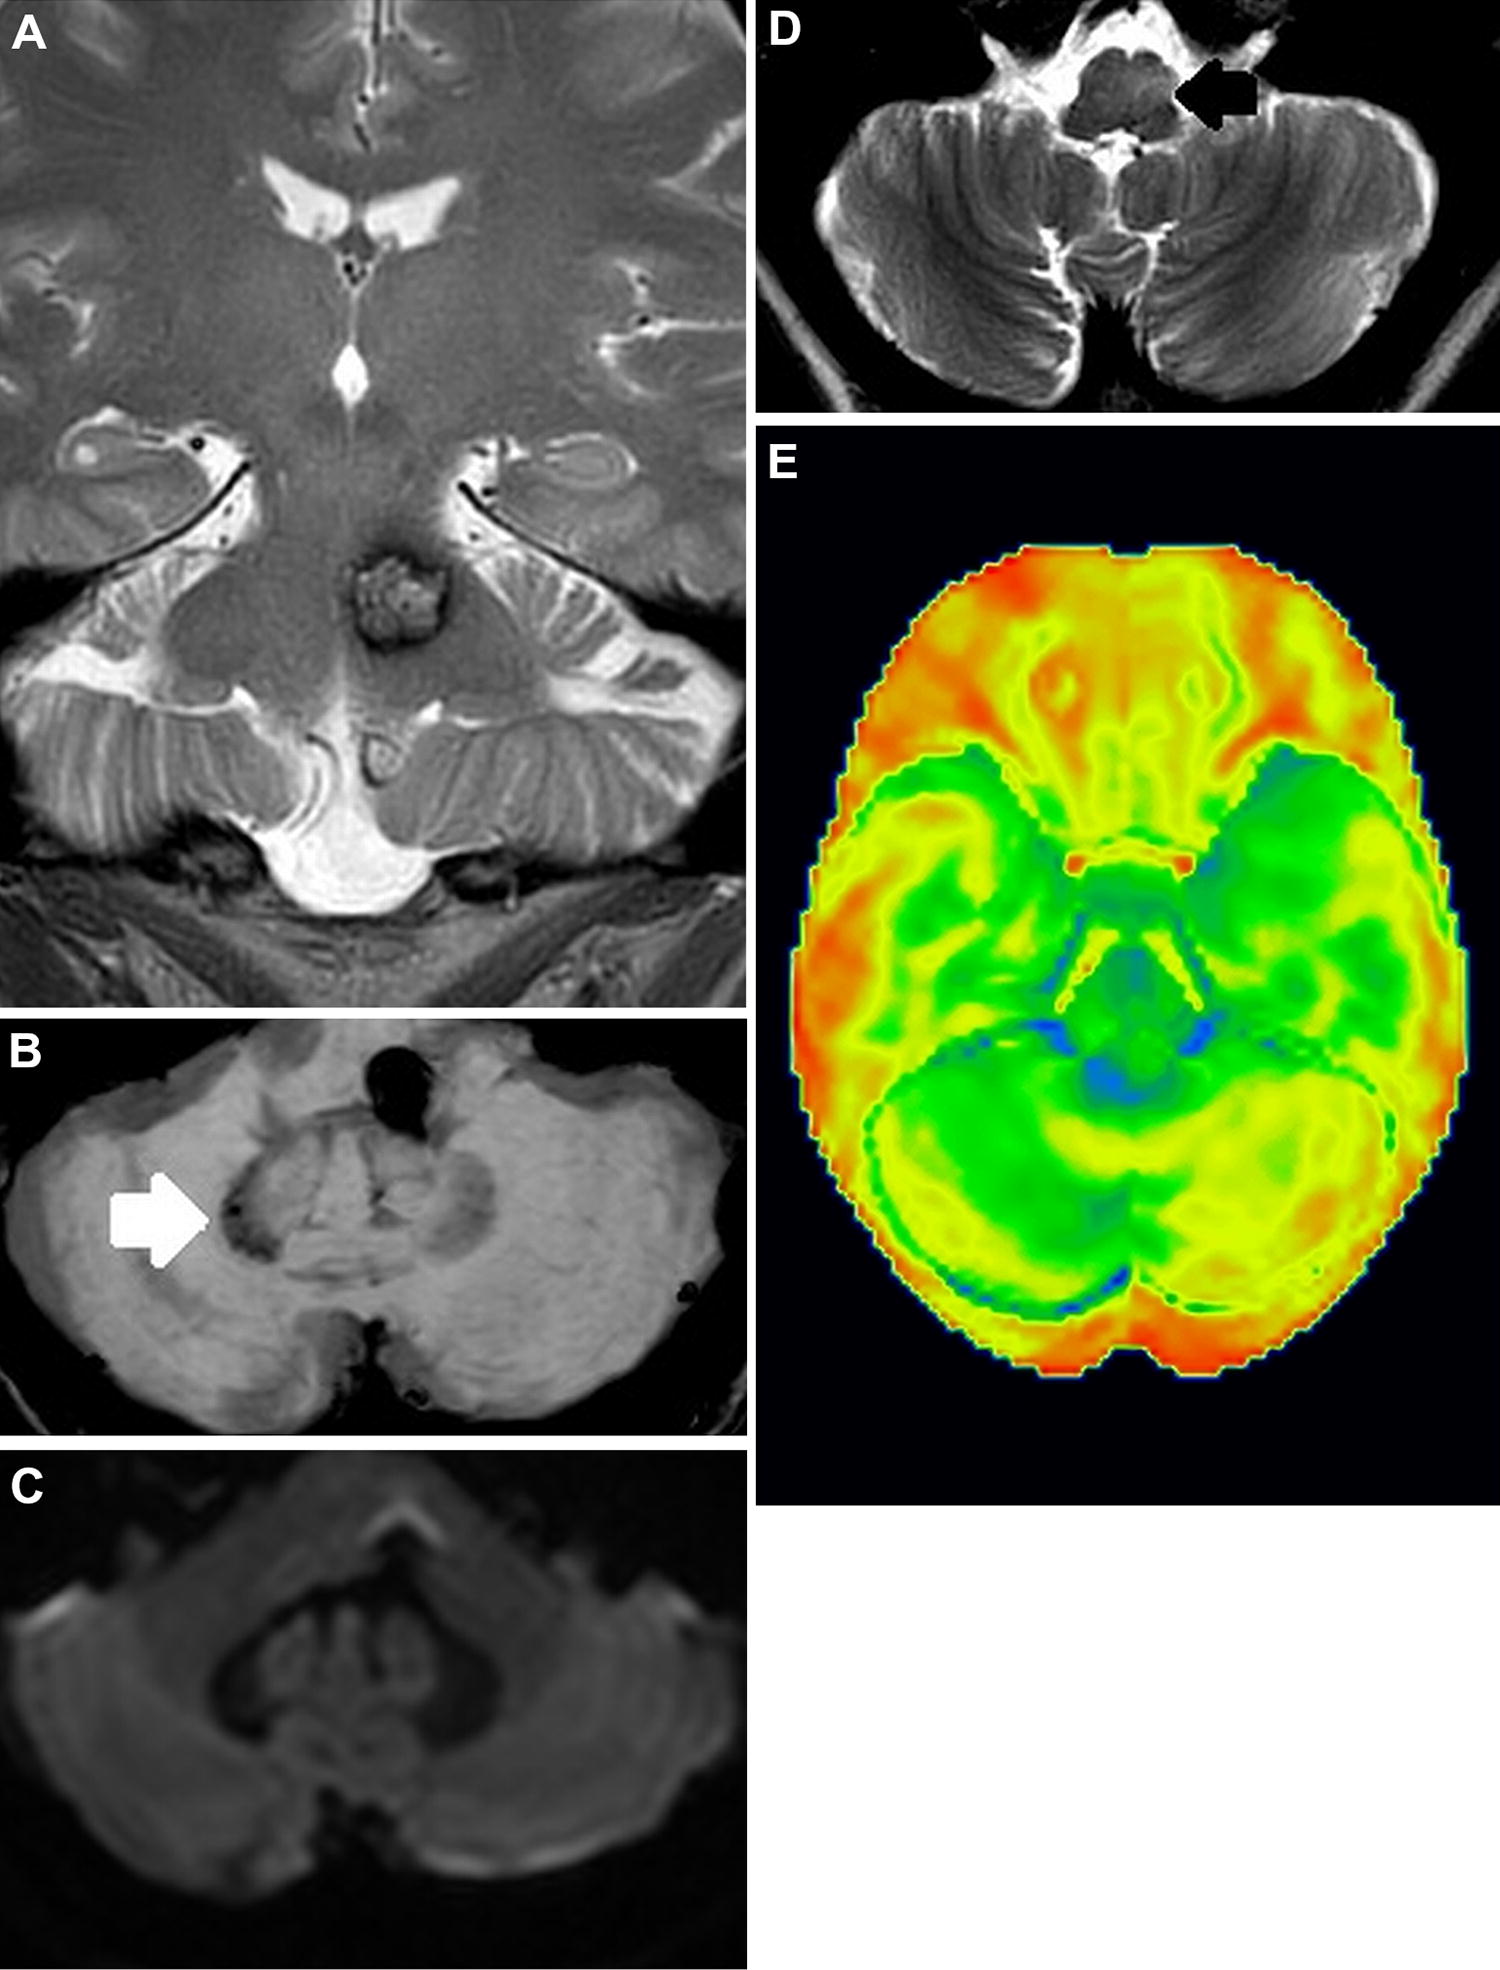

A 55-year-old woman presented with motor difficulties in the right arm and leg. She had a history of occipital headache and migraine; MRI of the brain 12 years earlier demonstrated an asymptomatic cavernous malformation in the tegmentum pontis, close to the left superior cerebellar peduncle (SCP) (Fig. 1a). She had marked difficulties with gait and handwriting. On clinical examination, irregular step length and decreased synkinesis were observed. The finger-to-nose test and finger tracking were atactic. She had right-sided limb ataxia, dysmetria and dysarthria.

Coronal T2-weighted (a), axial susceptibility weighted (b), diffusion-weighted (c) and axial T2-weighted (d) brain MRI. 18F-fluoro-deoxy-d-glucose positron emission tomography (e). The cavernous malformation in the left tegmentum pontis is seen (a) and the contralateral atrophy of the dentate nucleus (b, arrow and c). The left-sided hypertrophic olivary degeneration is demonstrated (d, arrow). 18F-fluoro-deoxy-d-glucose positron emission tomography shows right cerebellar hypometabolism (e)